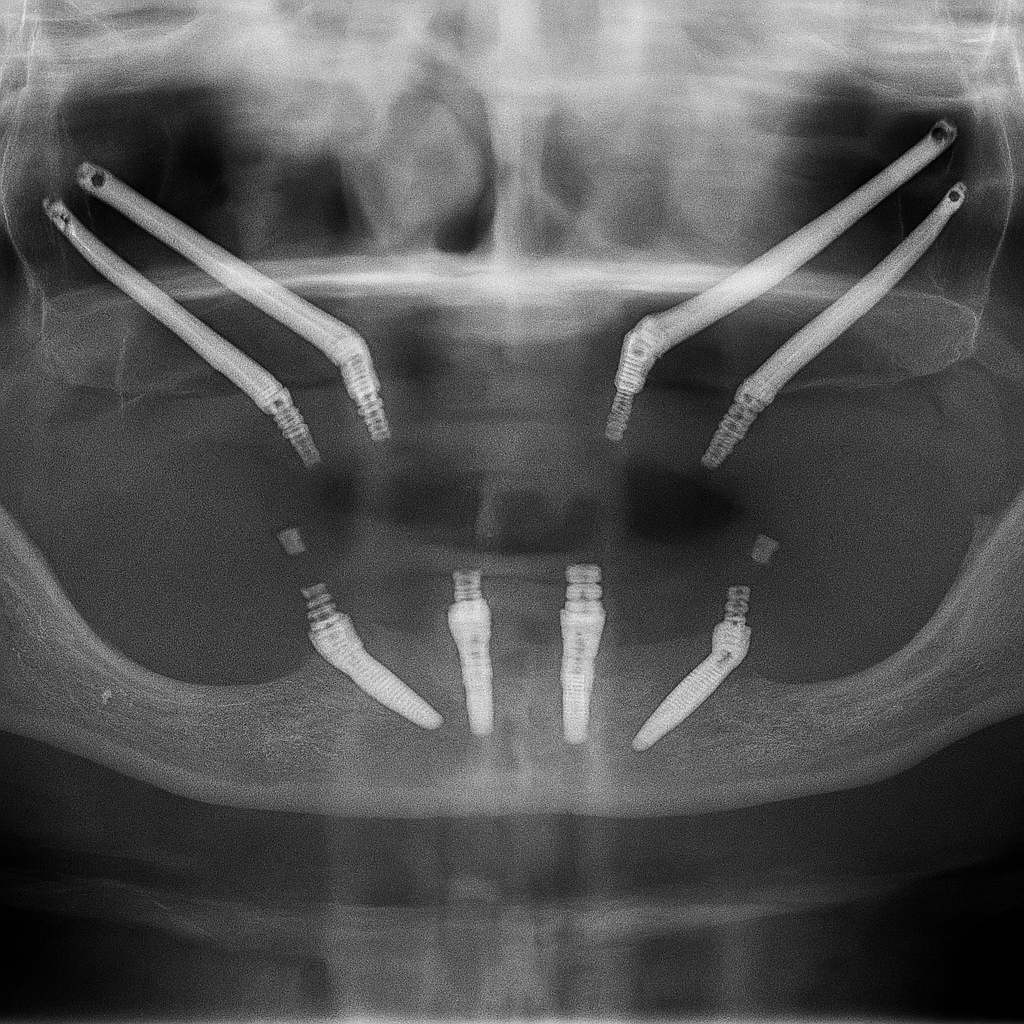

The main purpose of zygomatic implants is to offer a fixed, functional, and aesthetic prosthetic solution to a patient population that, until relatively recently, had very limited options. These patients, due to severe maxillary atrophy, are not viable candidates for the placement of conventional dental implants.

Zygomatic implants represent a cutting-edge solution in advanced oral implantology, designed specifically for the rehabilitation of patients with severe bone loss in the maxilla.

Uses native, dense bone The zygomatic bone provides strong cortical anchorage, creating an immovable base for long-span prosthetics, even after severe atrophy.

Graft-less pathway By bypassing large sinus grafts and iliac crest harvests, treatment time can shorten and morbidity can decrease compared to multi-stage augmentation plans.